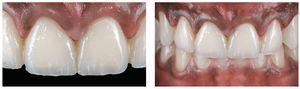

Figs. 9a a 9c. La situación 90 días después de la intervención quirúrgica y un blanqueamiento de dos semanas en casa. El recorrido gingival sigue la línea labial inferior y ya no se aprecia sonrisa gingival

Figs. 10a y 10b. El nuevo recorrido gingival.